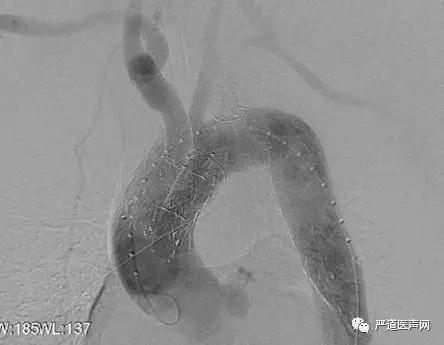

术中“模块内嵌主动脉弓覆膜支架”各个模块安全植入,释放过程稳定、无移位,模块之间稳定衔接。最后造影显示弓部动脉瘤被完全隔绝、无内漏、主体和分支血管通畅。

术中支架植入后造影结果